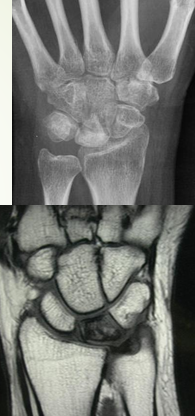

Wrist: Kienbock Disease

Pathophysiology: AVN/osteonecrosis of the lunate > leads to collapse

Causes: result of trauma/injury, abnormal vascular diseases OR by unequal radius and ulna lengths

X-rays

MRI